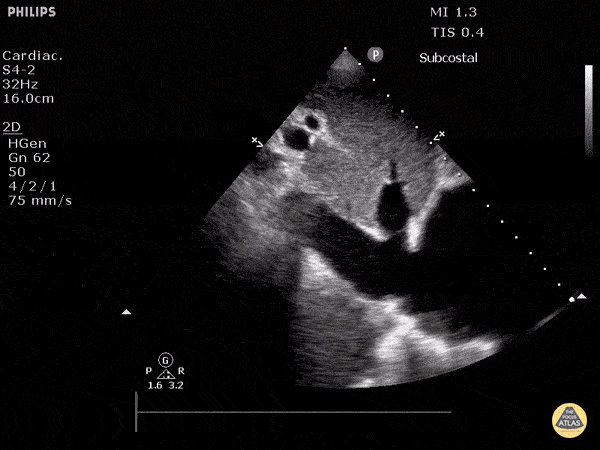

vci-starr